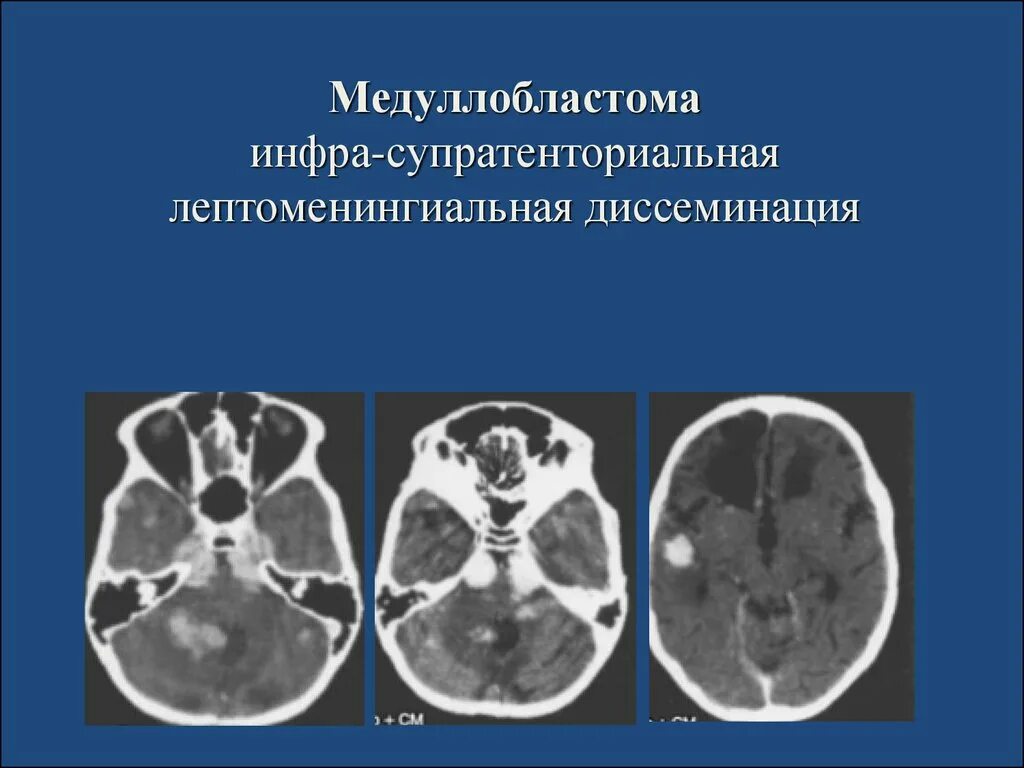

Медуллобластома это